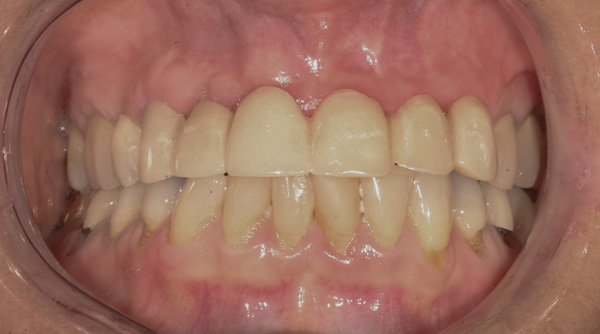

Background: This patient had a failing maxillary dentition and refused to wear a removable prosthesis. A staged approach was employed to retain some of his natural tooth abutments, and recession was noticed at the time of the impression for the second group of implants. Figure 1 shows the patient following insertion of the first set of implant custom abutments; the adjacent natural teeth are still present to support the provisional bridge. Seven months later, as shown in Figure 2, those first-stage custom abutments exhibited evidence of 1 mm to 3 mm of recession.

Figure 1 Patient following insertion of first set of implant custom abutments.

Figure 1